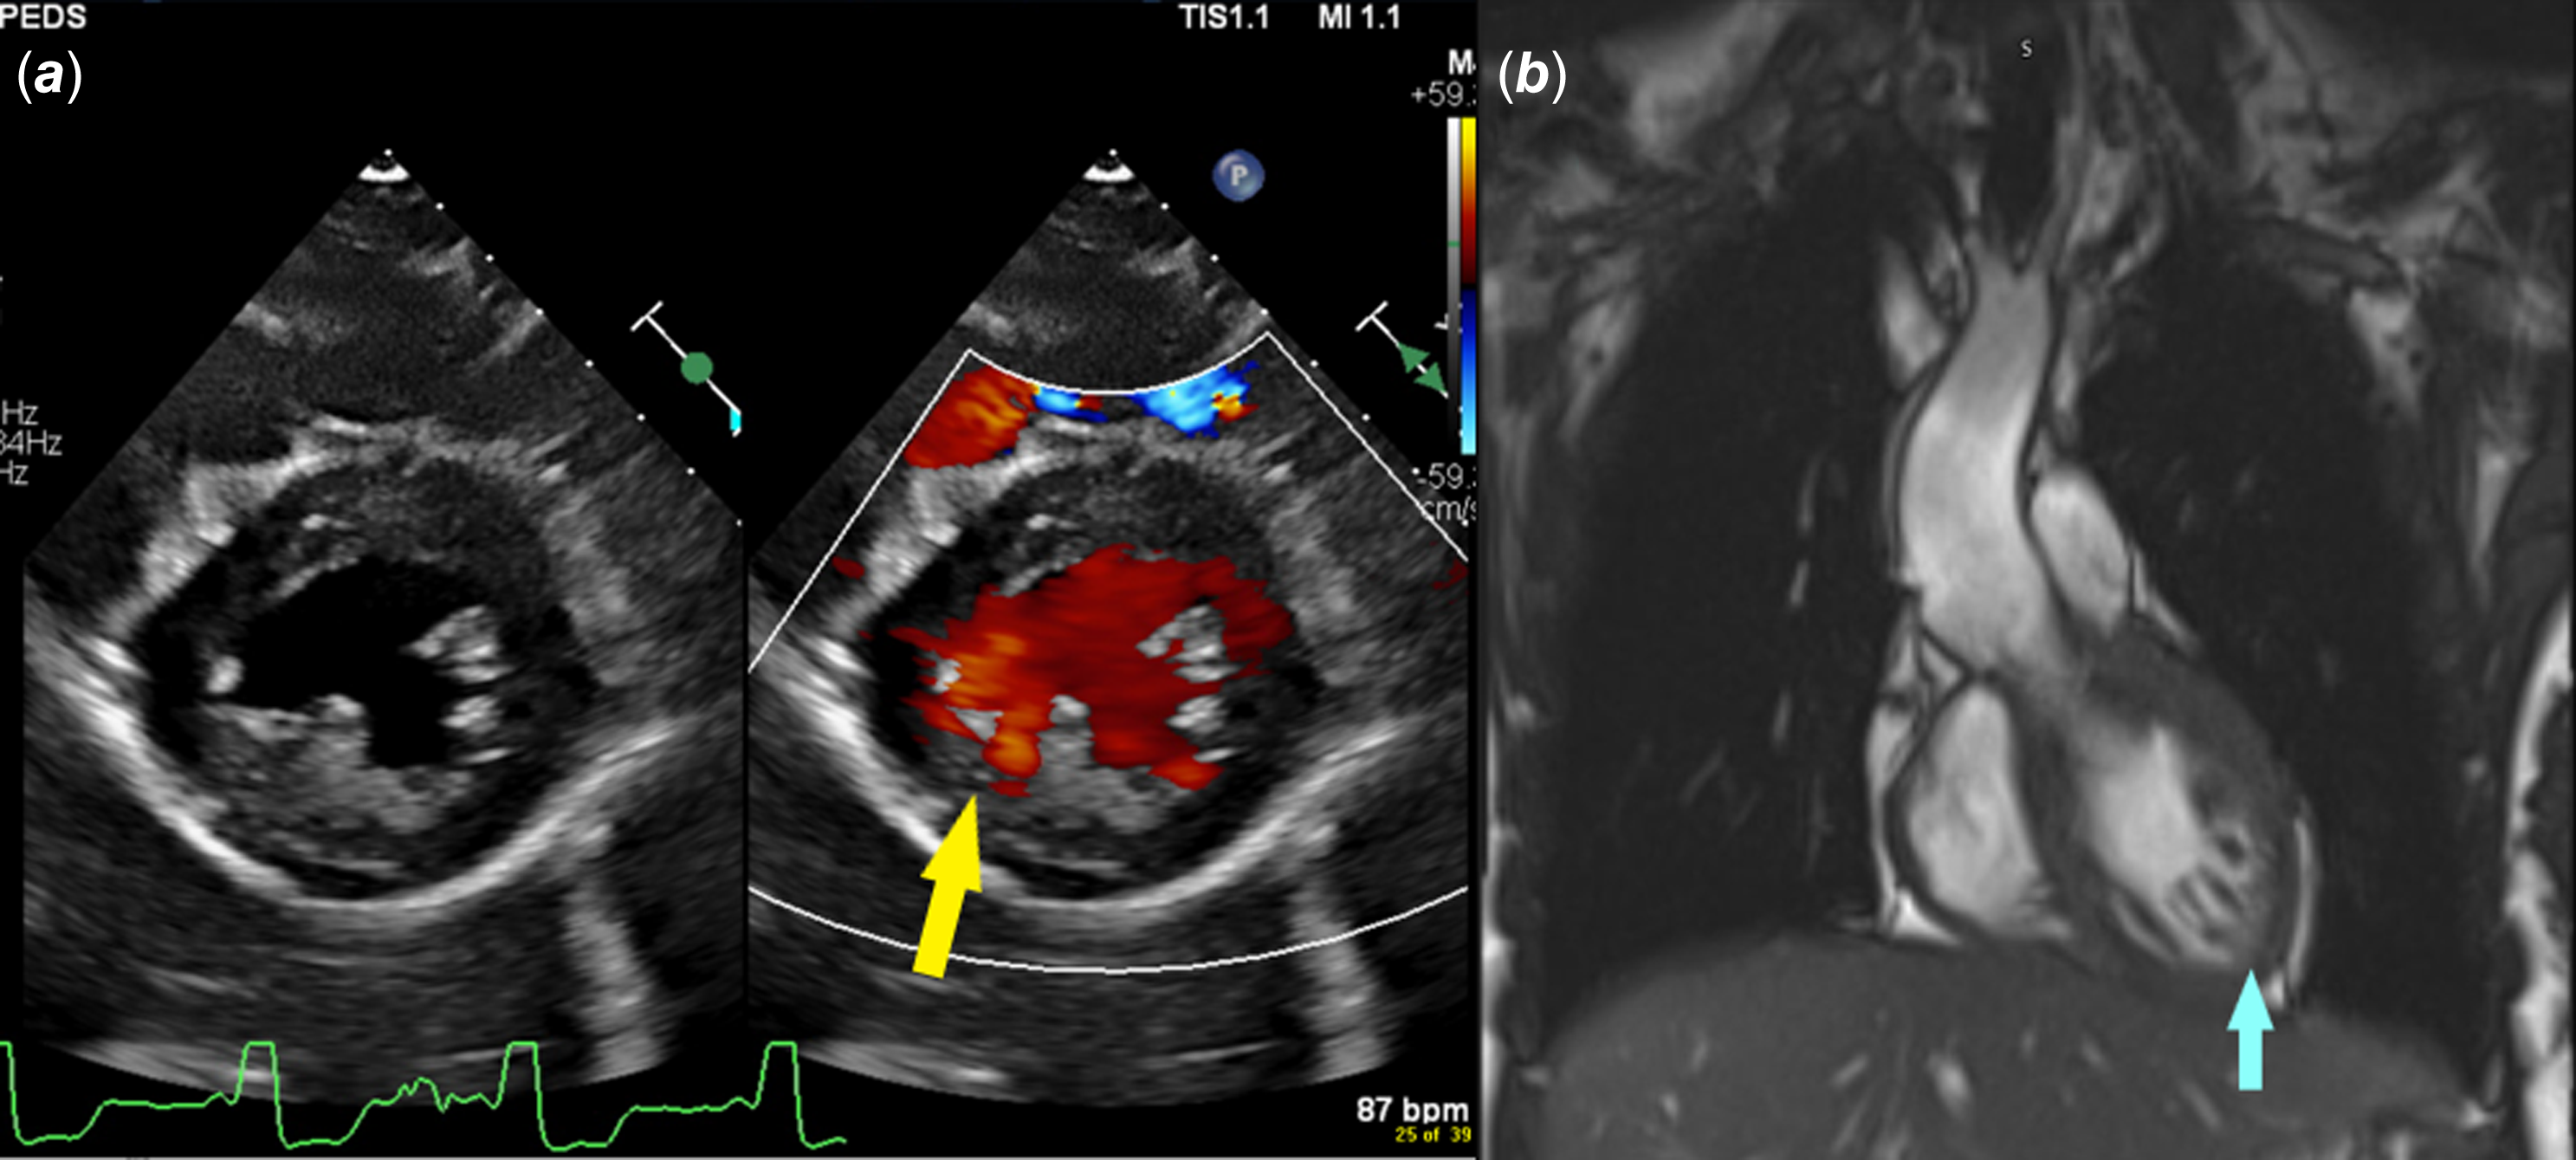

A 17-year-old girl presented with palpitations and Wolff–Parkinson–White pattern on electrocardiogram (Figure 1). Her echocardiogram was suggestive of left ventricular non-compaction with preserved ejection fraction (Figure 2A, Video 1). This was confirmed on cardiac magnetic resonance imaging per criteria proposed by Petersen et al (Figure 2B, Video 2).Reference Petersen, Selvanayagam and Wiesmann7 She underwent an exercise stress test during which pre-excitation persisted at a peak heart rate of 171 beats per minute suggesting a possible high-risk pathway. She subsequently underwent an electrophysiology study during which orthodromic reentrant tachycardia was induced (cycle length of 460 msec) with programmed atrial stimulation. On decremental atrial pacing, the accessory pathway block cycle length was < 200 milliseconds and the shortest preexcited RR interval during atrial fibrillation measured 174 msec (Figure 3), findings which confirmed the pathway to be high risk. The episode of atrial fibrillation resulted in haemodynamic instability and required immediate cardioversion. Mapping was therefore only performed during pre-excited sinus rhythm. Earliest ventricular activation during sinus rhythm was noted over a broad area in mid coronary sinus and superolateral mitral annulus. However, application of radiofrequency energy at these sites was not successful in eliminating pre-excitation (Figure 4). She was started on sotalol until she underwent another EP study a month later. This time, the earliest ventricular activation during sinus rhythm was recorded over a broad area located from 2 to 4 o’clock along the mitral valve annulus. Empiric radiofrequency ablation was performed at the site. Orthodromic reentrant tachycardia was induced following initial ablations (Figure 5A), but no tachycardia could be induced following consolidation of the site. No ventriculoatrial conduction was noted following consolidation. Anterograde accessory pathway conduction, however, persisted, but antegrade pathway block occurred at an atrial pacing cycle length of 450 msec suggesting that the pathway had been modified. Eighteen months following the second ablation, the patient presented to the emergency department in supraventricular tachycardia, which was terminated with adenosine (Figure 5B). She is currently treated with flecainide 75 mg twice daily and is doing well.

Figure 2. Panel A: parasternal short axis 2D echocardiographic still frame image with colour compare shows left ventricular non-compaction. With colour, flow is noted within crypts. Panel B: the diagnosis is confirmed on a cardiac MRI which shows a ratio of non-compacted mass to total mass of 34 % (> 25% diagnostic of non-compaction).